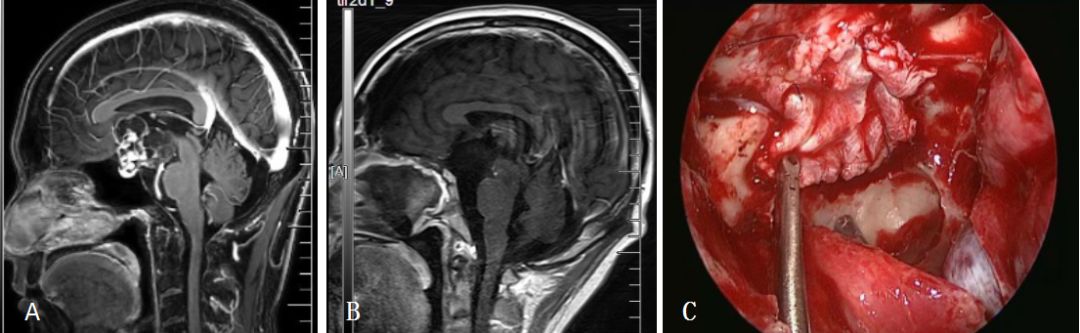

病例2:鞍结节脑膜瘤

图4. A:鞍结节脑膜瘤术前矢状位MRI;B:鞍结节脑膜瘤术后矢状位MRI;C:自体阔筋膜连续缝合修补颅底硬膜。